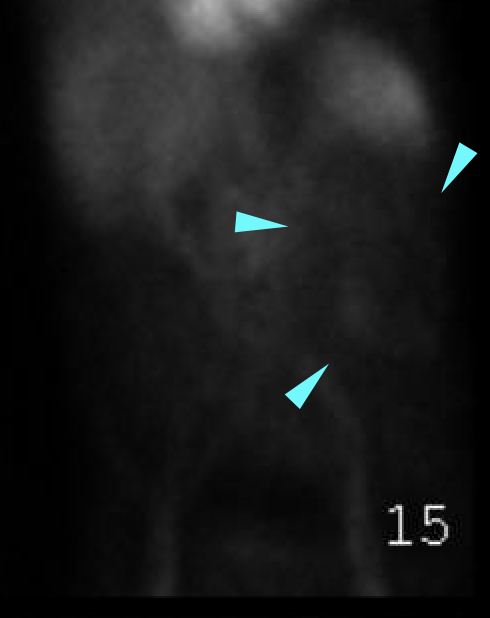

Age: 69

Sex: Male

Indication: GI bleeding

Radiotracer: Tc99m labeled RBCs

Sample ReportNo evidence of active GI bleeding during the course of this study.